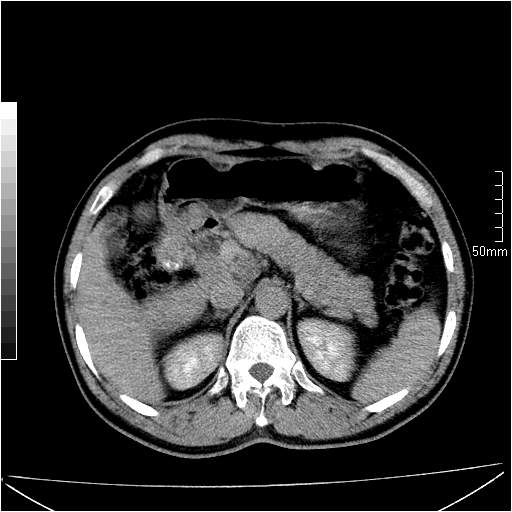

男性,54岁,皮肤黄染,搔痒一周余.b超示肝左叶回声异常.初步诊断1胆总管下段结石2胆囊结石伴慢性胆囊炎请各位战友帮忙看一下肝脏多发低密度如何解释恰当.增强效果不是很好.请大家见谅.

胆总管及肝内胆管扩张,考虑是结石!但,肝内的低密度区增强不明,可能是肝ca,因为肝ca在增强时呈快进快出.另年胆总管扩张原因,可以考虑一下是不是,胆管ca.再次要考虑肝内的低密度是否为海绵状血管瘤所致!

首先,胆总管下端结石梗阻伴肝内胆管扩张可确定。

另外,肝八段低密度占位,呈多灶性,考虑肝脓肿或肝癌可能,(图像质量欠佳)建议进一步检查。

既然做了增强,为什么光提供延时期片子,肝动静脉期肝右叶前下段病灶增强如何?另外胆囊壁增厚,欠规整,内密度不均,与肝右叶病灶分界不清,增强表现怎样?肝内胆管轻度扩张,胆总管扩张,但未见明显结石影,也应提供增强早期图像才好鉴别扩张原因。片子较清,但不够完整,暂考虑1.胆囊癌肝局部浸润,或肝癌胆囊侵犯,2.胆总管下端或胰头钩突部占位。总之本人看不明白,请高手画图指示,先谢了!

由于胆囊窝内结构显示不清,肝脏病灶又邻近胆囊窝首先考虑胆囊癌肝受侵犯。而后因肝脏病灶强化有渐进改变,且相邻胆管扩张,故考虑肝胆管细胞癌待排。

左肝胆管细胞癌。

胆总管下端结石。